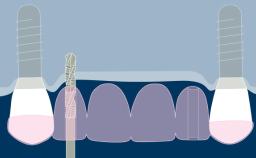

种植体印模对于义齿的制作很重要。种植体印模的目的是将口内种植体情况准确地传递给技工室。可以使用传统替代体印模技术或使用数字技术记录种植体情况。所有种植体印模技术均采用传统牙支持式修复中使用的开窗式或闭合式印模技术的变型。

在制取种植体印模时,使用精确制作的取模柱来记录种植体的位置、排列和角度方向。无论是遵循传统(即替代体)还是数字化印模制取流程,印模都会记录这些与周围硬组织和软组织相关的信息。本模块将介绍传统印模技术和所涉及的所有参数。

- 概述传统种植体印模的工作流程